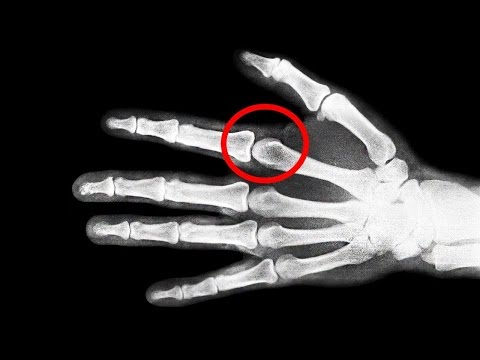

Probablemente eres parte del porcentaje de personas que a diario se crujen los dedos, y quizá, en mas de una ocasión te hayas preguntado si realmente hacerlo es malo o no para tus nudillos... En este video te hablaré de si es MALO crujirse los huesos de tus manos, y por ende, espero que tus dudas se resuelvan...